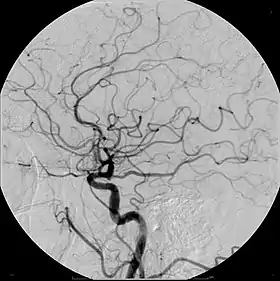

Example of iodine-based contrast in cerebral angiography | |

Digital subtraction angiography (DSA) is a fluoroscopy technique used in interventional radiology to clearly visualize blood vessels in a bony or dense soft tissue environment. Images are produced using contrast medium by subtracting a "pre-contrast image" or mask from subsequent images, once the contrast medium has been introduced into a structure. Hence the term "digital subtraction angiography.[1][2] Subtraction angiography was first described in 1935 and in English sources in 1962 as a manual technique. Digital technology made DSA practical starting in the 1970s.[3][4]

DSA is primarily used to image blood vessels. It is useful in the diagnosis and treatment of arterial and venous occlusions, including carotid artery stenosis, pulmonary embolisms, and acute limb ischaemia; arterial stenosis, which is particularly useful for potential kidney donors in detecting renal artery stenosis (DSA is the gold standard investigation for renal artery stenosis[10]); cerebral aneurysms and arteriovenous malformations (AVM).